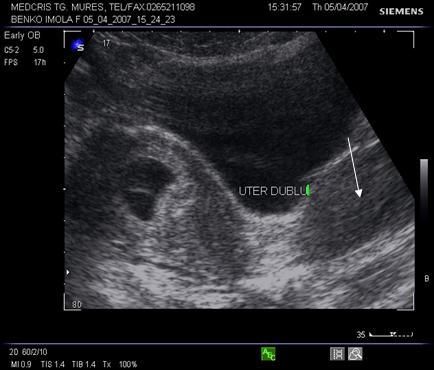

Sarcina va modifica aspectul ecografic al uterului malformat; in prezenta unui uter dublu, unul va contine un sac ovular, iar celalalt va avea un endometru ingrosat decidualizat.

Fig. nr. 102. Uter dublu cu sarcina la ecografia abdominala (aceeasi pacienta ca in figura precedenta) se remarca cu sageata corpul uterin negravid